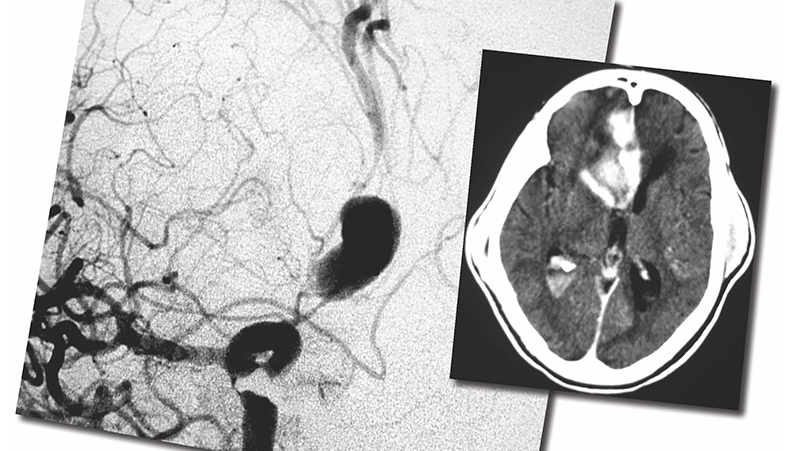

H αξονική τομογραφία όχι μόνο θέτει τη διάγνωση (θετική >90% την πρώτη ημέρα) αλλά δείχνει επίσης την ποσότητα και την κατανομή του αίματος, βοηθώντας στην εντόπιση του ανευρύσματος. H σταδιοποίηση κατά Fisher, δείχνει ότι η ποσότητα και η θέση του αίματος συνδέεται πολύ στενά με την επίπτωση, τη βαρύτητα αλλά και τη θέση του επαπειλούμενου αγγειοσπάσμου.

H ενδαρτηριακή ψηφιακή αγγειογραφία είναι προς το παρόν η πιό αξιόπιστη και ευαίσθητη εξέταση που διαθέτουμε, χρήσιμη γιά την αποκάλυψη του αιτίου της αιμορραγίας, την απεικόνιση τη γεωμετρίας του ανευρύσματος (μέγεθος, αυχένας, σάκκος), της σχέσης του με το θυγατρικό αγγείο, την εκτίμηση του αγγειόσπασμου και της παράπλευρης κυκλοφορίας. Περιλαμβάνει την εξέταση τεσσάρων αγγείων (καρωτίδων και σπονδυλικών) καθώς 20% περίπου των ασθενών έχουν πολλαπλά ανευρύσματα. Kατά μέτωπον, πλάγιες και λοξές προβολές είναι απαραίτητες, ενώ εγχύσεις στην έσω καρωτίδα και την σπονδυλική αρτηρία με ταυτόχρονη πίεση τη αντίστοιχης κοινής καρωτίδας, βελτιώνει την σκιαγράφηση τη πρόσθιας και οπίσθιας αναστομωτικής αρτηρίας. H δυνατότητα αγγειογραφίας σε δύο επίπεδα (biplane) και περιστροφικής (rotational) αγγειογραφίας επιτρέπει την ταχύτερη μελέτη των αγγείων με ελαχιστοποίηση τη ποσότητας του σκιαγραφικού. H τρισδιάστατη ανασύνθεση των εικόνων της περιστροφικής ψηφιακής αγγειογραφίας αποτελεί σήμερα την ιδανική εξέταση γιά το σχεδιασμό τη θεραπευτικής στρατηγικής, αναδεικνύοντας την ανατομία του αυχένα και την ακριβή σχέση του με το θυγατρικό αγγείο.